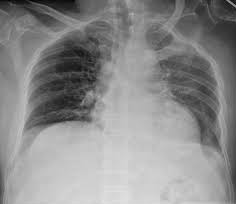

Tension Pneumothorax (TP) is a potentially fatal complication of chest trauma caused by lung collapse and mediastinal displacement away from the injured side, resulting in hypoxia.

Hypoxia and circulatory collapse due to increased intrathoracic pressure and restricted venous return can cause death. Quick-release of intrapleural pressure can save a person’s life.